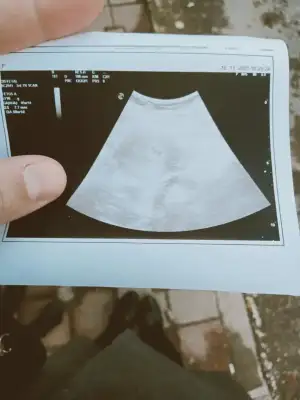

Adet döngü uzunluguda önemli bende benimde adetin 14 günü yumurtlama oldu 16 ekimde .. 30 ekim beklenen adet... 8 kasımda ise yani adetin gecikmesindeki 9 gunde kese gözüktü 4+6 da ama belli belirsiz hatta dr bana göstermedi bile kagıtta vermedi içim raht etmedi 5+1 de tekrar gittim busefer doktor gosterdi usg kagıdıda verdi kalp atıslarını duyana kadr evham yapmaya elimizden gelmeyerek devam edicez sanırım

bu alttakide son adet tarihine göre 5+1 kesede tam günü gününe uyumlu 5+1 cıktı bende cuma gidecegim sıradaki takıntım yolk varmı bebek varmı sonra bekle Allah ki kalp atısı varmı çok bilinçli olmakta bazen çok sıkıntı